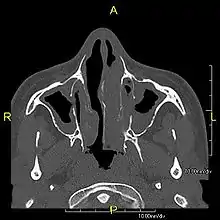

Around 80% of people with primary ciliary dyskinesia experience respiratory problems beginning within a day of birth. Many have a collapsed lobe of the lung and blood oxygen low enough to require treatment with supplemental oxygen.[1] Within the first few months of life, most develop a chronic mucus-producing cough and runny nose.[1] The main consequence of impaired ciliary function is reduced or absent mucus clearance from the lungs, and susceptibility to chronic recurrent respiratory infections, including sinusitis, bronchitis, pneumonia, and otitis media. Progressive damage to the respiratory system is common, including progressive bronchiectasis beginning in early childhood, and sinus disease (sometimes becoming severe in adults). However, diagnosis is often missed early in life despite the characteristic signs and symptoms.[2] In males, immotility of sperm can lead to infertility, although conception remains possible through the use of in vitro fertilization, there also are reported cases where sperm were able to move.[8] Trials have also shown that there is a marked reduction in fertility in females with Kartagener's syndrome due to dysfunction of the oviductal cilia.[9]

Many affected individuals experience hearing loss and show symptoms of otitis media which demonstrates variable responsiveness to the insertion of myringotomy tubes or grommets. Some patients have a poor sense of smell, which is believed to accompany high mucus production in the sinuses (although others report normal – or even acute – sensitivity to smell and taste). Clinical progression of the disease is variable, with lung transplantation required in severe cases. Susceptibility to infections can be drastically reduced by an early diagnosis. Treatment with various chest physiotherapy techniques has been observed to reduce the incidence of lung infection and to slow the progression of bronchiectasis dramatically. Aggressive treatment of sinus disease beginning at an early age is believed to slow long-term sinus damage (although this has not yet been adequately documented). Aggressive measures to enhance clearance of mucus, prevent respiratory infections, and treat bacterial superinfections have been observed to slow lung-disease progression. The predicted incidence is 1 in approximately 7500.[10]

Diagnosis

Several diagnostic tests for this condition have been proposed.[5] These include nasal nitric oxide levels as a screening test, light microscopy of biopsies for ciliary beat pattern and frequency and electron microscopic examination of dynein arms, as the definite diagnosis method. Genetic testing has also been proposed but this is difficult given that there are multiple genes involved.[6]

When accompanied by the combination of situs inversus (reversal of the internal organs), chronic sinusitis, and bronchiectasis, it is known as Kartagener syndrome[3] (only 50% of primary ciliary dyskinesia cases include situs inversus).[11]